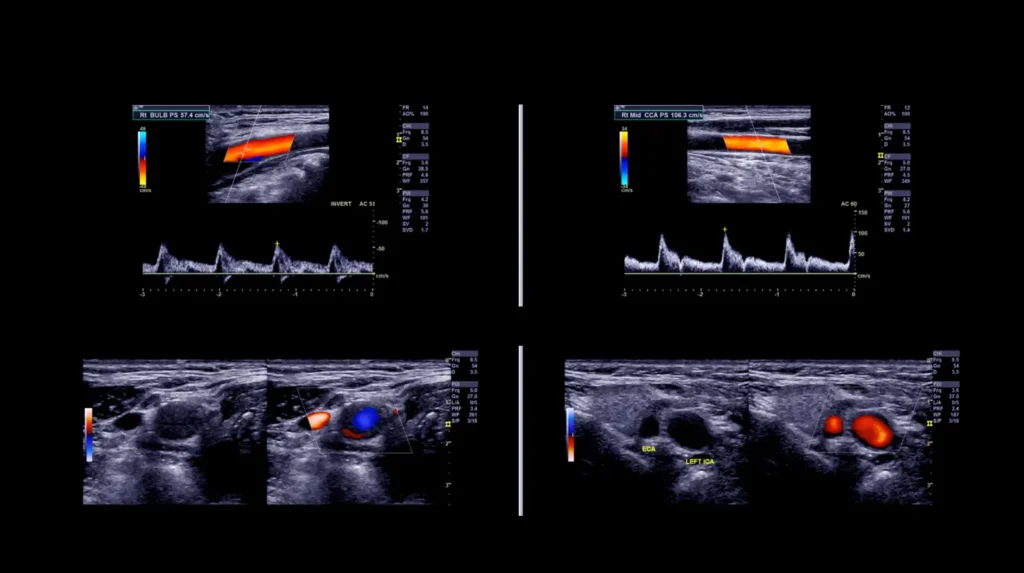

Il principio fisico si basa sulla variazione di frequenza degli ultrasuoni riflessi dagli eritrociti in movimento (effetto Doppler), dalla cui elaborazione è possibile ricavare velocità, direzione e turbolenza del flusso. La codifica cromatica sovrapposta all’immagine in scala di grigi facilita l’identificazione di stenosi, occlusioni, reflussi patologici e alterazioni della compliance vascolare.

Ecocolordoppler dei Tronchi Sovraortici

L’ecocolordoppler di carotidi è un esame indispensabile per valutare la salute delle arterie carotidee, responsabili dell’afflusso di sangue al cervello. Serve per individuare eventuali restringimenti o placche aterosclerotiche, riducendo il rischio di ictus.